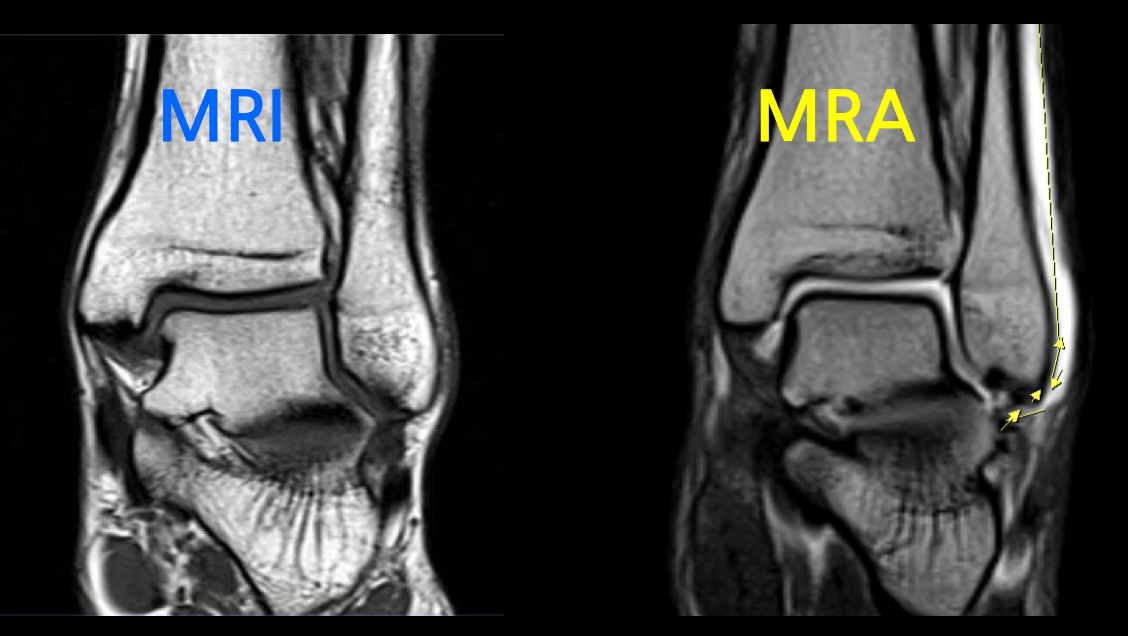

MRA는 MRI와는 다르게 조영제를 사용하며 특히, 같은 부위를 촬영하더라도 조영제 유무에 따라서 촬영된 영상 이미지에 큰 차이가 존재합니다.

작고 좁은 관절에 연부조직을 확인하기 위하여 조영제를 사용하며, 손상여부 및 정도를 확인할 수 있습니다.

정형외과에서 MRA는 어깨, 팔꿈치, 발목과 같은 관절에 적용합니다. 초음파로 확인하기 어려운 관절 전체구조를 확인하고 관절 내 이상소견 및 연부조직 손상여부, 감염등을 확인하는데 큰 도움을 줍니다.

어깨, 팔꿈치, 발목 관절에 조영제를 주입하여 MRI를 촬영하면 조영제가 손상된 틈으로 스며들어 관절 속 미세한 병변까지 진단할 수 있습니다. 이를 관절조영증강 MRI 또는 MRA(Magnetic Resonance Arthrogram)이라고 부릅니다.

- 발목 : 외상으로 인한 인대 손상 및 관절낭(관절막) 손상, 관절연골 손상